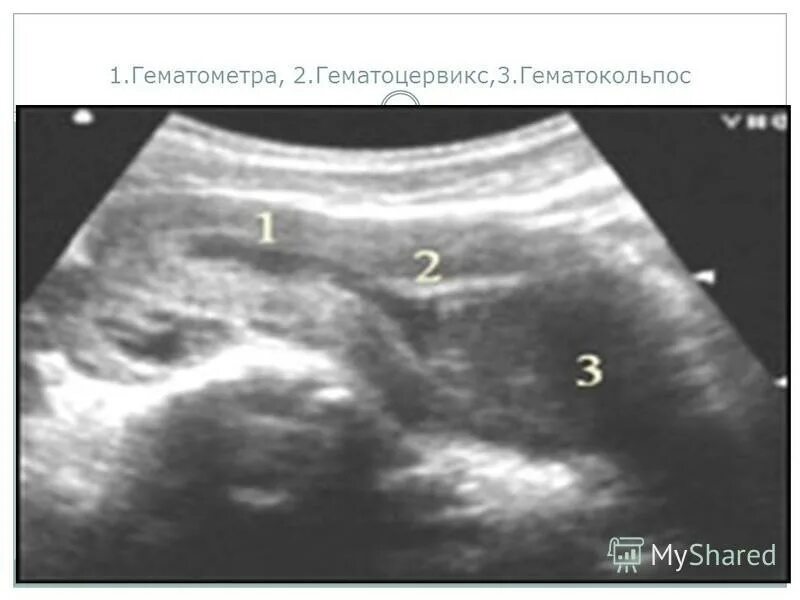

Гематометра симптомы